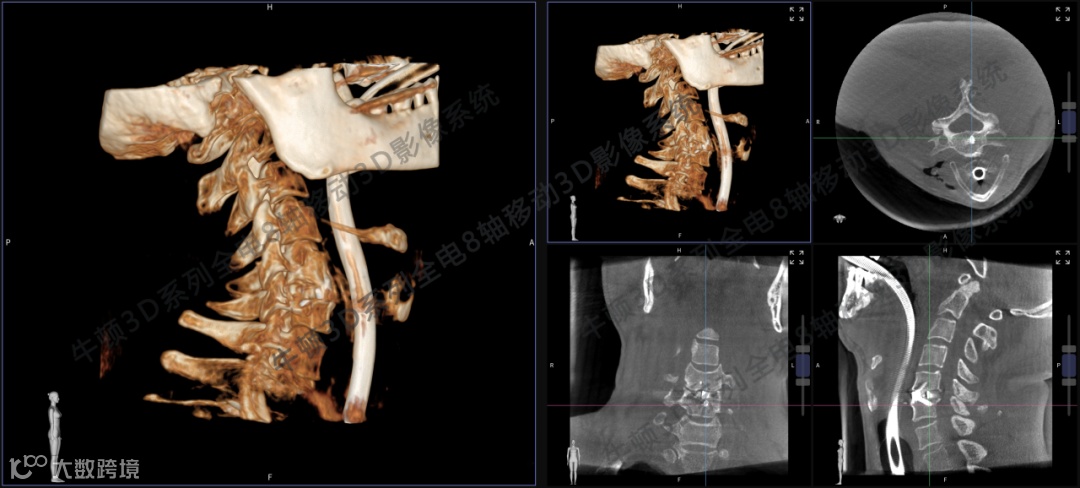

三维影像案例1:颈椎间盘突出ACDF术后,手术区域三维结构清晰呈现,帮助医生轻松了解手术减压效果及内固定位置。